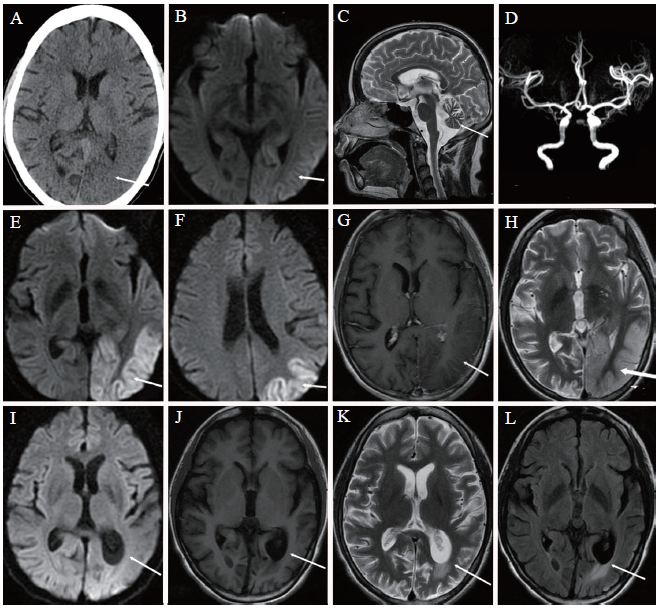

图1 一例MELAS患者的影像学检查

A ~ D:发病3 d后;A:脑CT示左侧颞枕叶低密度(箭头);B:磁共振弥散加权成像(DWI)显示左侧颞枕叶高信号(箭头);C:MRI T2加权像显示小脑半球明显萎缩(箭头);D:MRA示左侧大脑后动脉远端分支较右侧增多;E ~ H:发病1周后;E:MRA示左侧大脑中动脉远端分支较右侧增多(箭头);F:左侧颞顶枕叶皮层DWI高信号,较前进展(箭头);G:增强MRI左侧颞枕叶病灶未见明显强化(箭头);H:MRI T2加权像左侧颞枕叶高信号(箭头);I ~ L:发病3个月后;I:左侧颞顶枕叶DWI等信号,左侧侧脑室后角扩大(箭头);J:MRI T1加权像左侧颞顶枕叶皮层等信号,左侧侧脑室后角扩大(箭头);K:MRI T2加权像左侧侧脑室后角局部脑组织呈高信号;L:MRI液体衰减反转恢复序列左侧侧脑室后角局部高信号,提示胶质增生(箭头)

患者女,33岁。因头痛3 d、视物不清2 d于2020年4月5日入我院。患者于入院前3 d无明显诱因出现头痛,为左侧颞枕部持续性胀痛。入院2 d前开始出现视物不清,伴精神烦躁、反应迟钝。于当地诊所接受止痛、补液等对症处理后病情无明显好转,遂来我院。急诊颅脑CT:①左侧颞枕叶低密度影;②双侧小脑萎缩。脑MRI:①左侧顶枕颞叶大片异常信号,扩散加权成像(DWI)病灶弥散受限;②双侧小脑半球萎缩。磁共振血管造影(MRA):左侧大脑中动脉、大脑后动脉远段分支增多(图1A ~ D)。急诊以“头痛、视物不清查因:脑炎?”收入院。患者起病以来无发热、抽搐,进食少,睡眠减少。否认有头痛史,否认有高血压、糖尿病、心脏病史。自幼不能耐受体力活动,有反应稍迟钝及可疑听力下降,但从未接受诊治。高中文化。父母健在,母亲有“糖尿病”史,姐姐有“头痛”史。已婚,育有一女,配偶及女儿身体健康。

实验室及辅助检查:血、尿、大便常规及肝肾功能、电解质、血氨、梅毒+HIV抗体、血糖均无异常,心电图、X线胸片以及心、腹、泌尿系统超声检查均无异常。2次血乳酸检测分别为0.8、1.2 mmol/L(我院正常参考值0 ~ 2 mmol/L)。肌酸激酶373 U/L(50 ~ 310 U/L)、CK-MB 137 U/L(0 ~ 24 U/L),乳酸脱氢酶353 U/L(120 ~ 250 U/L)。肌钙蛋白正常。甲状腺功能正常。甲状腺球蛋白抗体466.9 IU/ml(0 ~ 115 IU/ml)、甲状腺过氧化物酶抗体414.2 IU/ml(0 ~ 34 IU/ml)。甲状腺超声:甲状腺回声异常,双叶实性结节,部分钙化,考虑结节性甲状腺肿。腰椎穿刺检查:压力150 mm H2O(1 mm H2O = 0.0098 kPa),无色透明。脑脊液常规与生化检查:白细胞3×106/L、总蛋白 0.28 g/L、葡萄糖4.64 mmol/L、氯117 mmol/L。单纯疱疹病毒PCR DNA(-),脑脊液病原体宏基因组二代测序(-),血液及脑脊液自身免疫性脑炎抗体(-)。4月9日完善脑MRI增强扫描+磁共振波谱成像:左侧顶枕颞叶大片异常信号影,较前进展,增强扫描未见强化(图1E ~ H)。当日因患者躁动,磁共振波谱成像未能完成,后拒绝再次检查。结合患者既往有活动后易疲劳、听力减退、反应稍迟钝,肌酶明显增高,影像学提示双侧小脑明显萎缩,脑MRI示左侧颞枕叶皮质及皮质下病变,定位于脑和肌肉。结合本次卒中样发作,有头痛,精神状态改变,视野改变,诊断考虑MELAS可能性大。因患者不能配合行听力测定、肌电图检查,不同意行脑磁共振波谱检查及肌肉活组织检查,故联系广州金域公司行外周血线粒体脑肌病基因测序。

患者入院后予辅酶Q10胶囊20 mg、每日3次,艾地苯醌30 mg、每日3次,维生素E 50 mg、每日3次,三磷酸腺苷二钠20 mg、每日3次,并予高碳水化合物、高蛋白营养支持等治疗。治疗1周后患者头痛缓解,视物改善,病情好转出院,出院后继续服用辅酶Q10胶囊及艾地苯醌。1个月后基因检测结果报告:线粒体DNA3243位点发生突变,m.3243A > G,突变比例36%,最终确诊为MELAS。患者出院3个月后复诊,病情明显改善,神志清晰,对答切题,视物清晰,无头痛,无新发症状,简易精神状态评价量表(MMSE)评分20分。7月2日复查脑MRI:左侧侧脑室后角扩大,周围脑组织萎缩、胶质增生(图1I ~ L)。纯音电测听提示双耳轻度感音性耳聋。